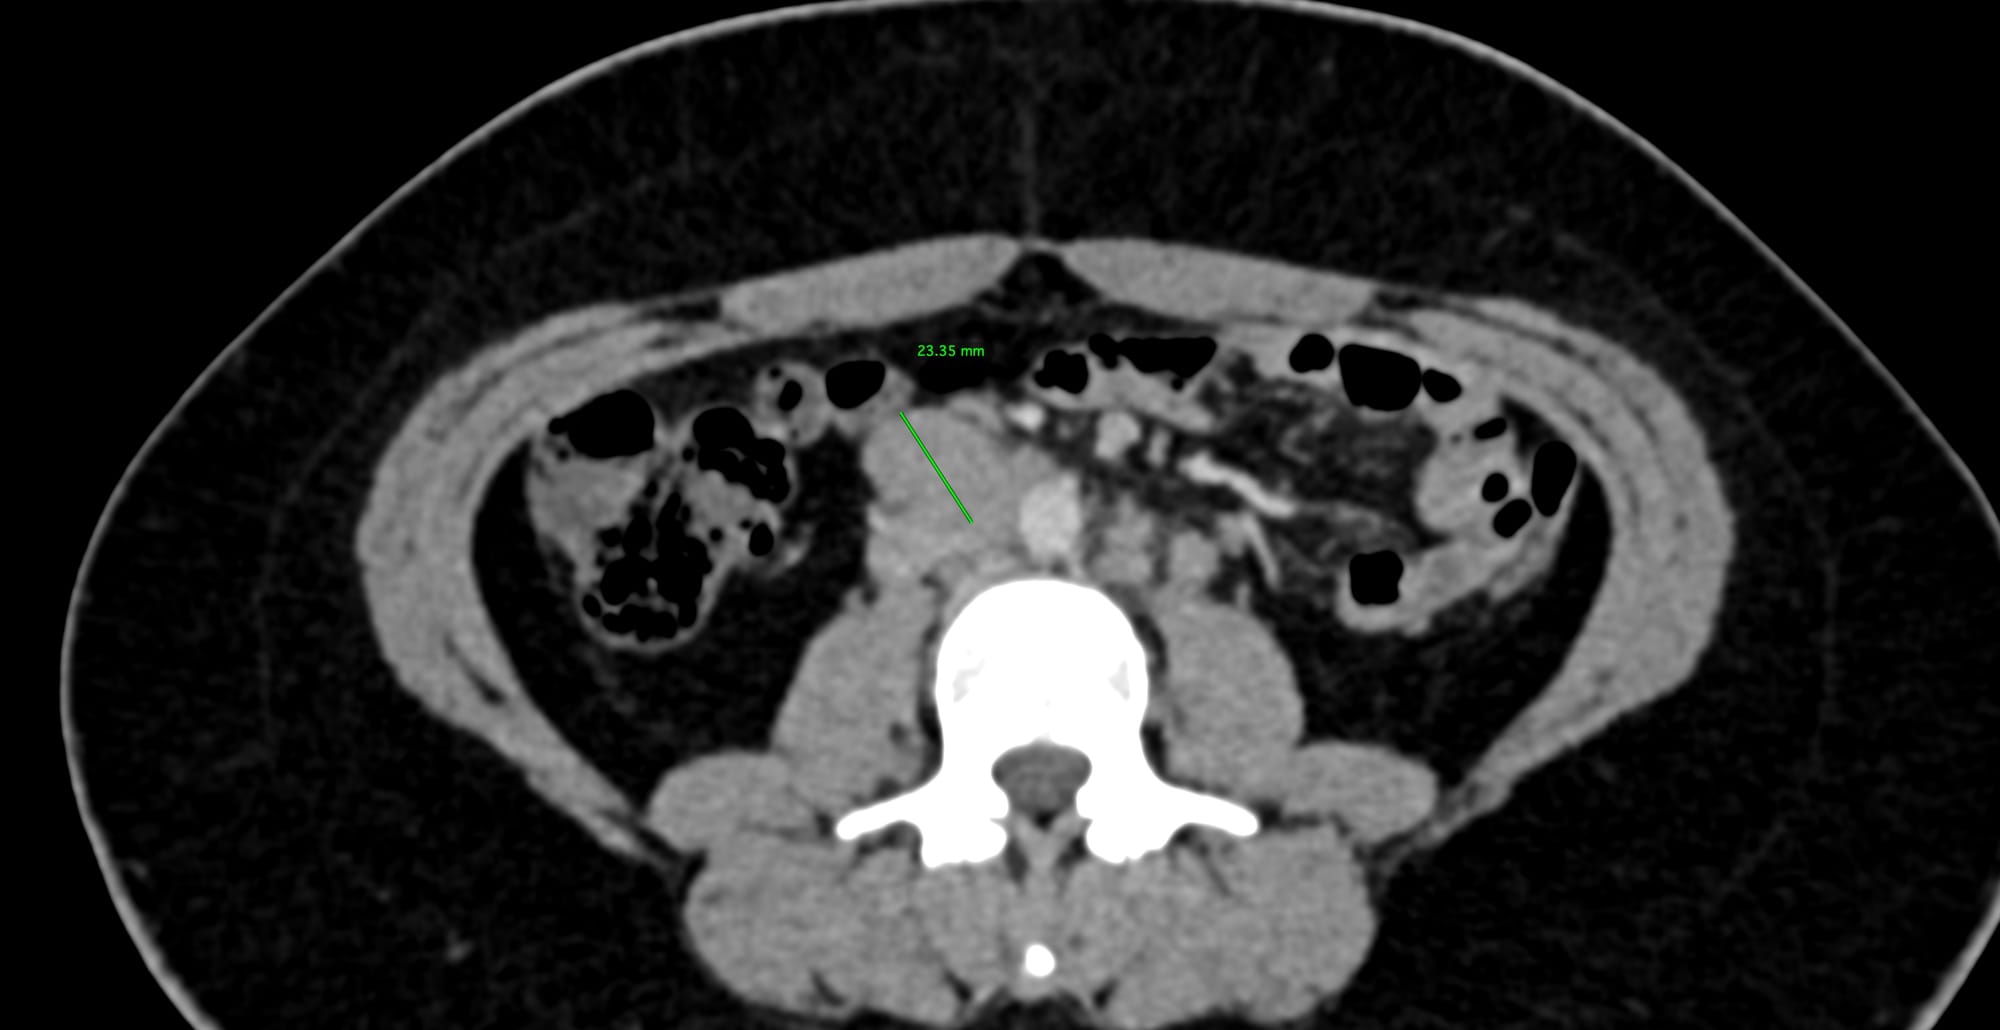

Fig. 3 shows the AP diameter. The posterior margin has a vein draining into the IVC, so care has to be taken not to overshoot.